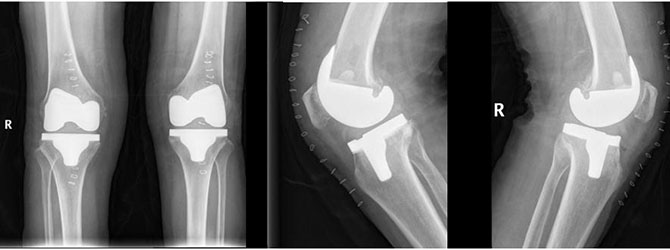

全膝关节置换及膝关节翻修置换术,适用于病变累及膝关节多个间室,或者是同时合并韧带软组织损伤的情况。手术能够针对病变膝关节进行彻底清除病变,明显改善患者多年疾病困扰。具有稳定畸形关节、缓解关节疼痛、纠正严重畸形、提高生活质量等临床优势。